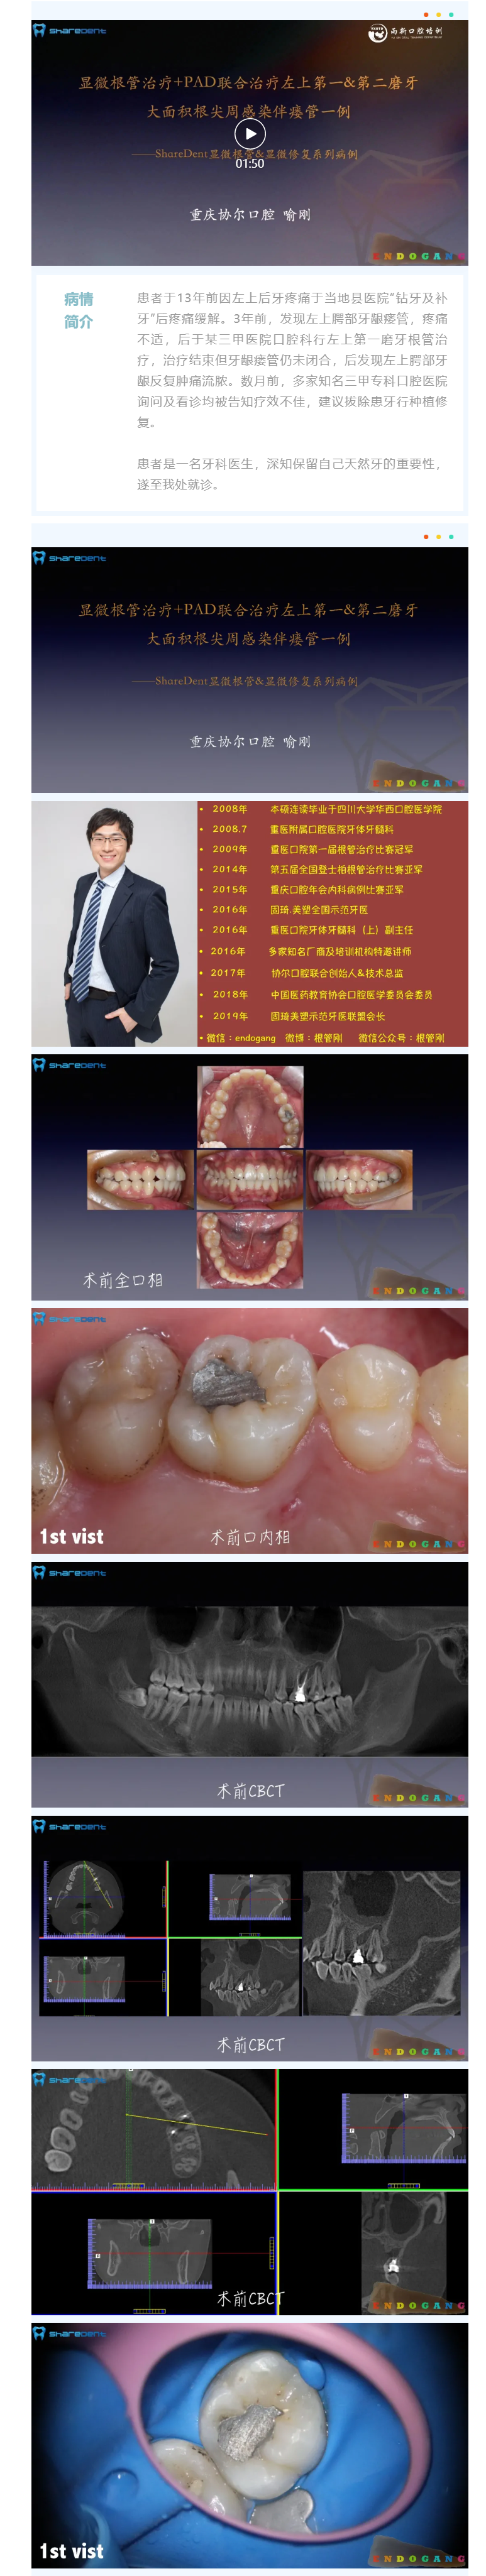

激光、显微、美学树脂,集合所有大招,只为保住天然牙